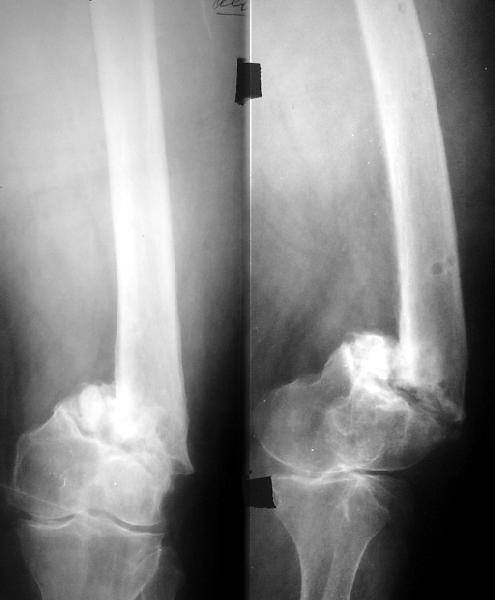

Пациентка 72 года поступила в клинику с диагнозом несросшийся в условиях остеосинтеза перелом н/3 правой бедренной кости, перелом фиксатора ( в анамнезе 3 неудачные операции на бедре по поводу вышеуказанного диагноза). Интересует Ваше мнение по поводу тактики лечения пациентки.

Здесь вполне можно не вмешиваться открыто. Сделать fixator-assisted nailing. Все закрыто убрать. Хорошо восстановить ось. Через медуллярный канал ручными развертками освежить концы отломков. И заштифтовать. Раз уже был ретроградный стержень - то ретроградно. Я бы взял большеберцовый гвоздь, чтобы ввести винты в разных плоскостях. Ну и гвоздь потолще, и винты 6 мм.

Вот давний пример похожего ложного сустава после неоднократных остеосинтезов.

Александр здравствуйте! Вы представили очень интересный случай, отличный рентгенологический и функциональный результат. Меня смущает только достаточно выраженный гонартроз, как в случае с Вашей пациенткой так и с моей.

Еще раз смотрю на снимки - здесь практически диафизарный псевдатртроз. На вид не самый бесперспективный. Онкологический протез тут - из пушки по воробьям. Можно даже сделать остеосинтез, и в эту же сессию, или с отсрочкой, не дожидаясь сращения - стандартное эндопротезирование.